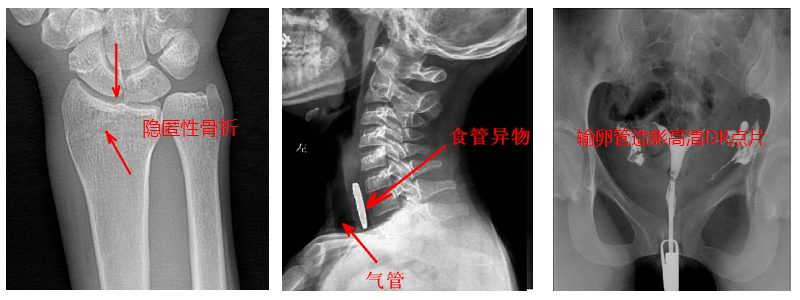

2.?dāng)?shù)字透視。適用于全身各部位透視(如胸透、腹透等),以及在透視下DR點片等;動態(tài)采集速度≥25幀/秒,應(yīng)用于消化科、泌尿科、婦科等。

4.?dāng)?shù)字造影。PLD5500B動態(tài)DR機適用于各種普通及特殊造影,如口服膽囊造影、靜脈膽道造影、T管造影、逆行胰膽管造影(ERCP)、靜脈腎盂造影(IVP)、子宮輸卵管造影、脊髓造影等,主要應(yīng)用于消化內(nèi)外科、泌尿外科、婦科、神經(jīng)內(nèi)外科等。

5.準(zhǔn)確點片。在透視下準(zhǔn)確找到病灶部位,這對于早發(fā)現(xiàn)隱匿性骨折有著不可替代的作用。更難能可貴的是,它可以在透視情況下進(jìn)行整骨復(fù)位以及術(shù)后在透視下檢查。